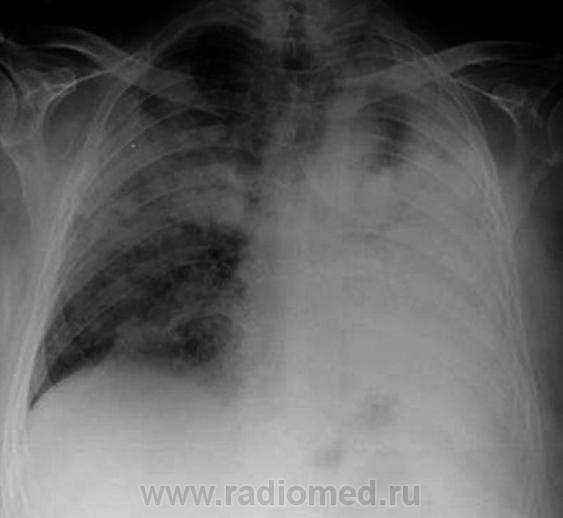

В УБ была произведена рентгенограмма в прямой стандартной проекции. Боковую не делали...

Жаль, что нет боковых снимков. На прямых не вижу молочных желез. Онкология с поражением обоих легких и ателектазом левого легкого. Насчет жидкости точно не скажу, но сердце смещено влево...

Терапевты по клинике выставляли двустороннюю пневмонию, но как-то не все укладывалось а данную нозологию. А, по рентгенограмме, слева, увидев "воздушную" бронхограмму, так и рентгенолога уговорили по поводу "пневмонии".

Нет, терапеты в УБ, выставили "пневмонию", рентгенолаборант сделал снимок. Рентгенолог, который приезжает "описывать снимки" колебался между пневмонией и бронхиолоальвеолярным раком, настаивая на дообследовании. Вот пациента, прямиком и отвезли на КТ, родственники натояли.

koriatus, неужели Вы не видите стрикулы, так характерные для онкологии? Инфильтрации как таковой нет. Почему ателектаз верхней доли, как раз слева на верхушке прослеживается легочная ткань? А ателектаз только дополняет картину, и настраивает в первую очередь на онкологию.